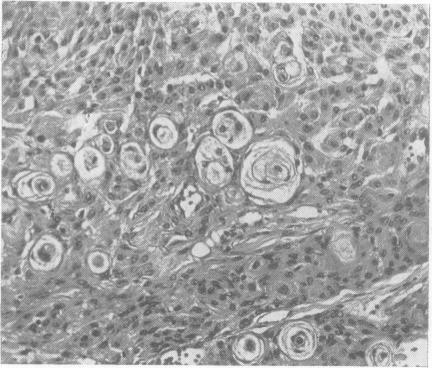

FAMILIAL MENINGIOMAS.

J Neurol Neurosurg Psychiatry. 1965 Apr;28(2):163-4. doi: 10.1136/jnnp.28.2.163.